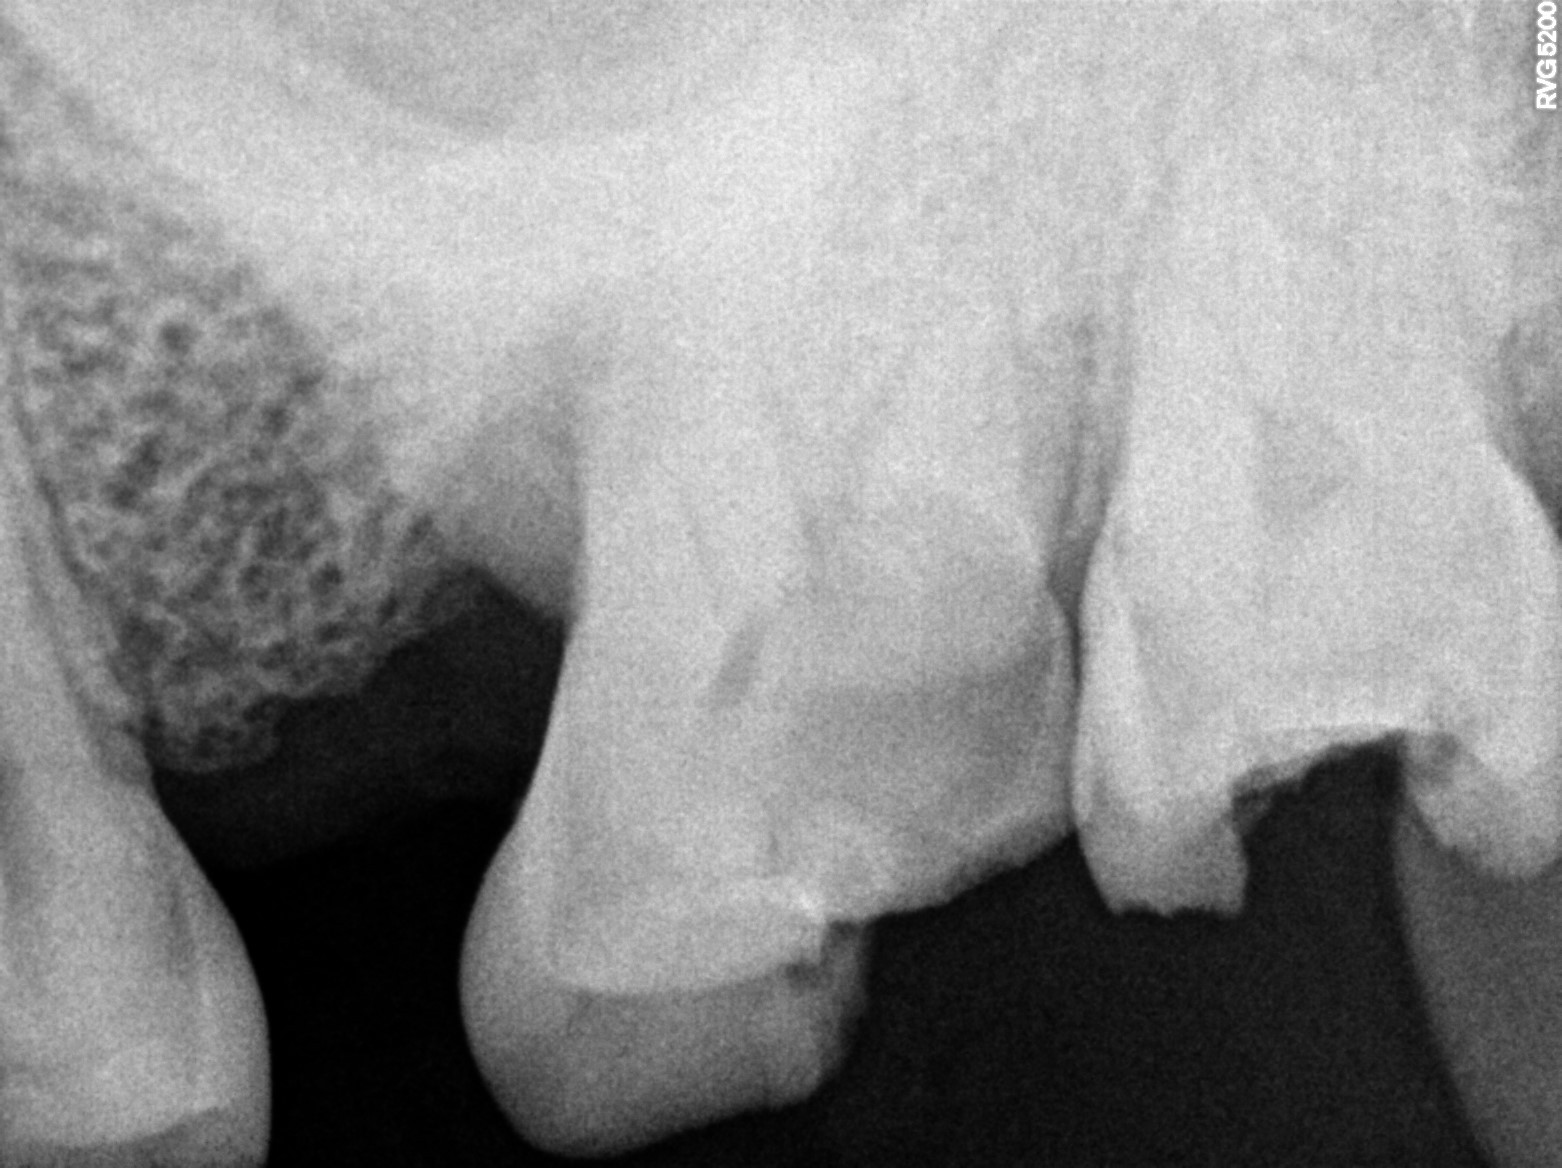

| Necrosis of dental pulp | K04.1 | 234946006 | resolved | 2026-03-17 | a/o with 27, bmp mb 0.5 stopper db 1 stopper palatal 2 stopper 20.06 all three canals |

| Root canal treatment | 234780006 | D3330 Endodontic therapy, molar tooth | ##27 | 2026-03-17 | completed | a/o with 27, bmp mb 0.5 stopper db 1 stopper palatal 2 stopper 20.06 all three canals |

| 2026-03-17 14:20 | fulfilled | a/o with 27, bmp mb 0.5 stopper db 1 stopper palatal 2 stopper 20.06 all three canals — Dr Riyaz |

Dental Radiographs FHIR: DocumentReference · LOINC 24641-7

xray_1773736623_0.jpg

24641-7